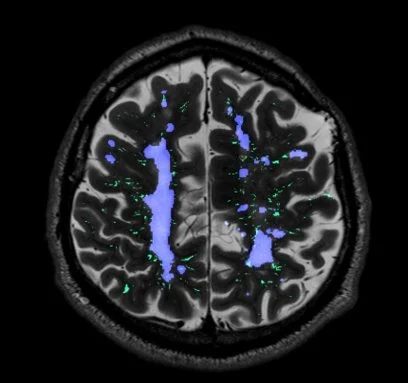

Our lab investigates the complex interplay between cerebral small vessel disease (CSVD) and neurodegeneration, with a focus on how vascular pathologies such as arteriolosclerosis and cerebral amyloid angiopathy (CAA) contribute to Alzheimer’s disease and related dementias. Ultimately, our goal is to uncover novel targets for early intervention and prevention of cognitive decline.

Ongoing studies aim to elucidate the mechanisms by which microvascular injury is linked to the accumulation of proteinopathies like amyloid-β and tau, with an emphasis on brain clearance dysfunction and blood brain barrier leakage. Furthermore, we investigate the role of subcortical vascular pathology and enlarged perivascular spaces in driving white matter injury. To address these questions, we employ a multimodal approach, combining in vivo and ultra-high-resolution ex vivo neuroimaging, AI-based quantitative pathology, three-dimensional histology, and super-resolution microscopy.